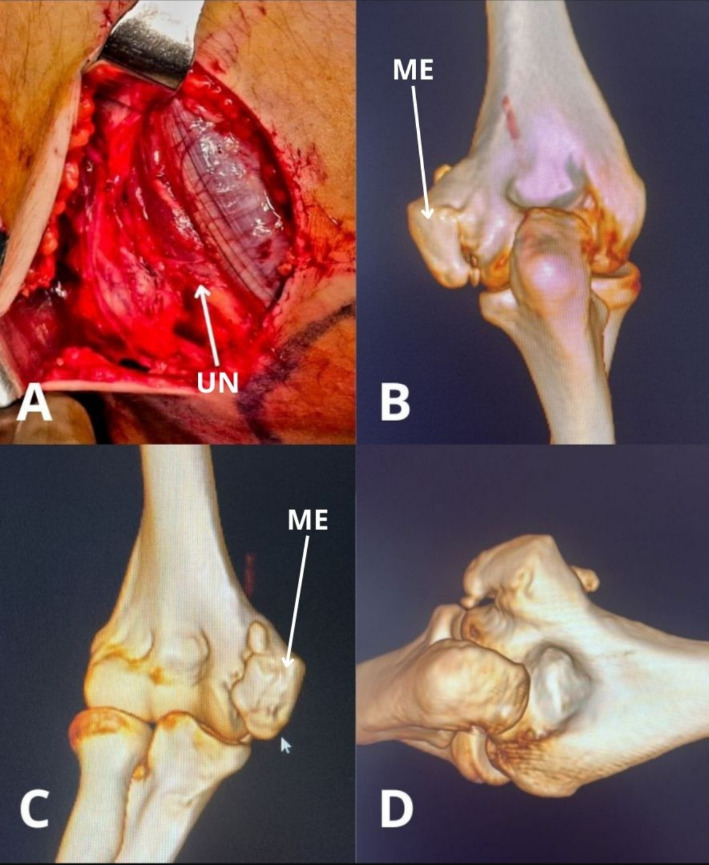

The classification system of heterotrophic ossification that would aid in treatment planning is represented by three classes, ranging from asymptomatic findings with heterotrophic ossification to complete ankylosis with or without ulnohumeral/forearm motion.22 The American Shoulder and Elbow Surgeons (ASES) also introduced standardized assessment guidelines to evaluate elbow function.23 Regarding imaging, the standard included anteroposterior and lateral radiographs.1,7,8 On the contrary, the use of computed tomography (CT) imaging would be superior when the contractures exceed 30 degrees or heterotrophic bone is present, as well as when physeal injury is suspected in skeletally immature patients or children.1,7,8 Ultrasound or electroneuromyography could be helpful to evaluate the ulnar nerve. Magnetic Resonance Imaging (MRI) is rarely used but may be reserved for the evaluation of inflammatory causes or soft tissue pathologies.1,7,8 In the child and adolescent, MRI is more often used as an accessory imaging modality to reliably measure the angle of the trochlear notch. Imaging modalities like MRI and 3D CT reconstructions are crucial when assessing joint morphology, bony impingement, or avascular necrosis, for which an example case is shown in Figure 2.

One of those factors is the etiology of elbow stiffness, as this varies between adolescents and adults and may influence the choice and timing of the procedure. In adolescents, common causes of stiffness include osteochondritis dissecans (OCD), avascular necrosis (AVN) following supracondylar fractures, deformities from malunion, fishtail deformity, or secondary effects of chemotherapy.5,9,11 In our experience, the majority of cases in the adolescent patient is due to malunion, nonunion or pseudoarthrosis of a medial epicondyle fracture. In contrast, adult patients more frequently present with stiffness due to degenerative conditions such as synovial chondromatosis, heterotopic ossification, or post-operative complications.7,14,17 In addition, adolescent patients usually have better tissue quality, better healing response, and may tolerate minimally invasive procedures like arthroscopic arthrolysis more effectively.